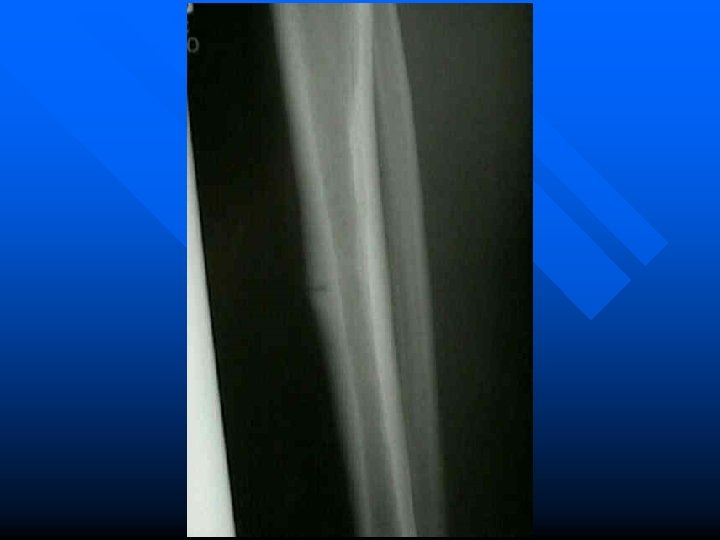

Leg Fractures n. Direct blows or indirect trauma

Stress Fractures An incomplete break in a bone occurring after prolonged repetitive exercise